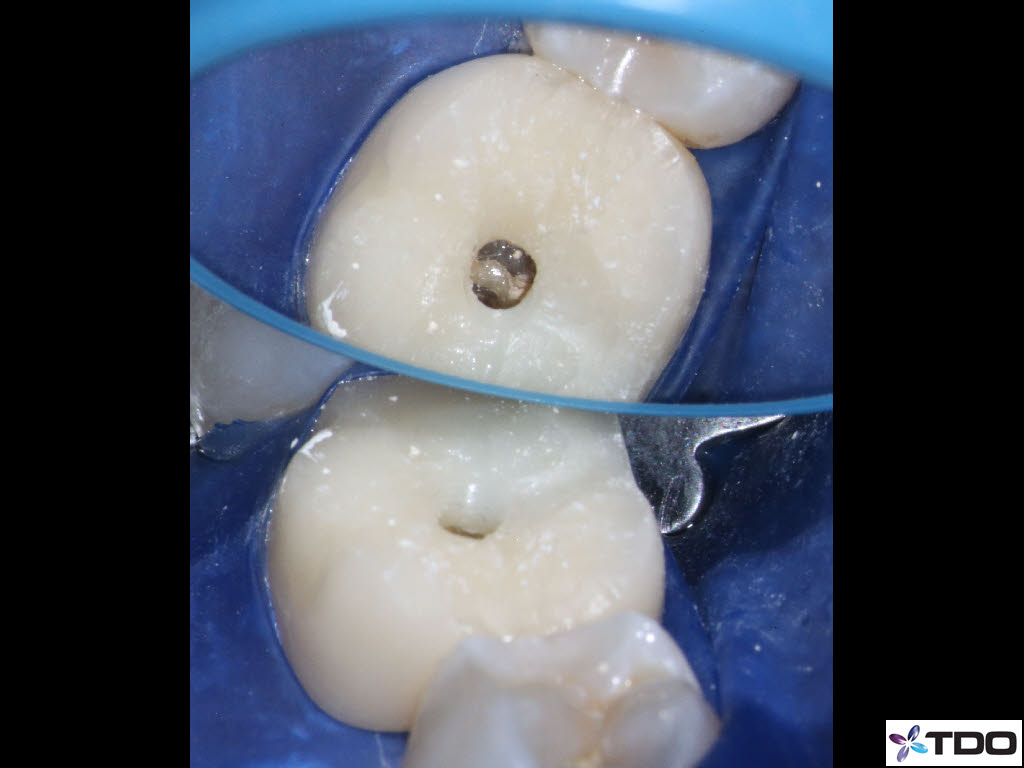

In the hierarchy of dentin conservation the existing restorative has the lowest priority and it quite frankly gets in the way of our access to the root canal system. But, after practicing directed dentin conservation for a while, you sometimes get lucky. The patient is 40yo. She was symptomatic at the time of treatment and interestingly the mesiobuccal canal was partially vital while the mesiolingual, distobuccal and distolingual canals were partially necrotic. She was asymptomatic at the completion visit as well as at the follow-up appointments.